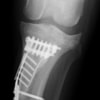

6歳 Mix犬 3.5kg

[主訴]

散歩で駆け出した後にキャンと鳴いてから右後肢を挙上しているとのことで来院。

[検査]

触診検査 MPL左右GradeⅡ

レントゲン検査 にて

右脛骨前方変位あり、ファットパッドサインあり

脛骨公平部角(TPA)の急峻を認める

[治療]

検査結果から前十字靱帯の断裂を疑い脛骨高平部水平化骨切り術(TPLO)を実施することに。また、パテラの安定化のために縫工筋内側広筋切開、滑車溝形成術も併せて実施。

[手術]

前十字靱帯部分断裂

半月板は大きな損傷なし

Fixin T字プレート使用して固定

・術後レントゲン

手術前TPA 28.4° が術後TPA 11.7° に矯正されました。

術後1週間で退院。現在は経過観察中です。

術前TPA計測

手術前

術後TPA計測

手術後

当院ではFixinmicroプレートを使用して小型犬のTPLO手術を実施しております。